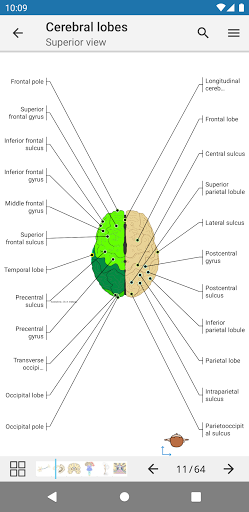

e-Anatomy tiene más de 26 000 imágenes que contienen series de imágenes en vistas axiales, coronales y sagitales, así como radiografías, angiografías, imágenes de disección, gráficos anatómicos e ilustraciones. Todas las imágenes médicas fueron etiquetadas cuidadosamente, más de 967 000 etiquetas disponibles en 12 idiomas, incluida la Terminologia Anatomica latina.

- Desplácese por los conjuntos de imágenes arrastrando el dedo

- Acerque y aleje el zoom

- Toque las etiquetas para mostrar las estructuras anatómicas

- Seleccione las etiquetas anatómicas por categoría